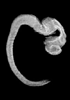

Carnegie Stage 17 (41 post-ovulatory days)

Most embryos at stage 17 are approximately 41 postovulatory days old and measure 11-14 mm in length. Distinguishing criteria for this stage include distinct digital rays in the hand plate, a rounded digital plate in the foot, a complete complement of hillocks on the mandibular and hyoid arches, distinct nasofrontal grooves, and a slight indication of a lumbar curvature.

This specimen does not represent normal development. The caudal nueral tube has failed to close properly.